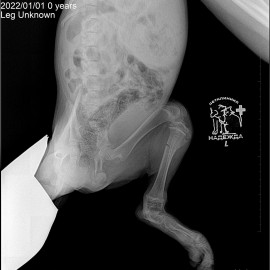

Обратились в нашу клинику с жалобами на отсутствие опороспособности на левую тазовую конечность.

После проведенных исследований был поставлен диагноз: перелом левой голени.

Снимок 1 до операции.